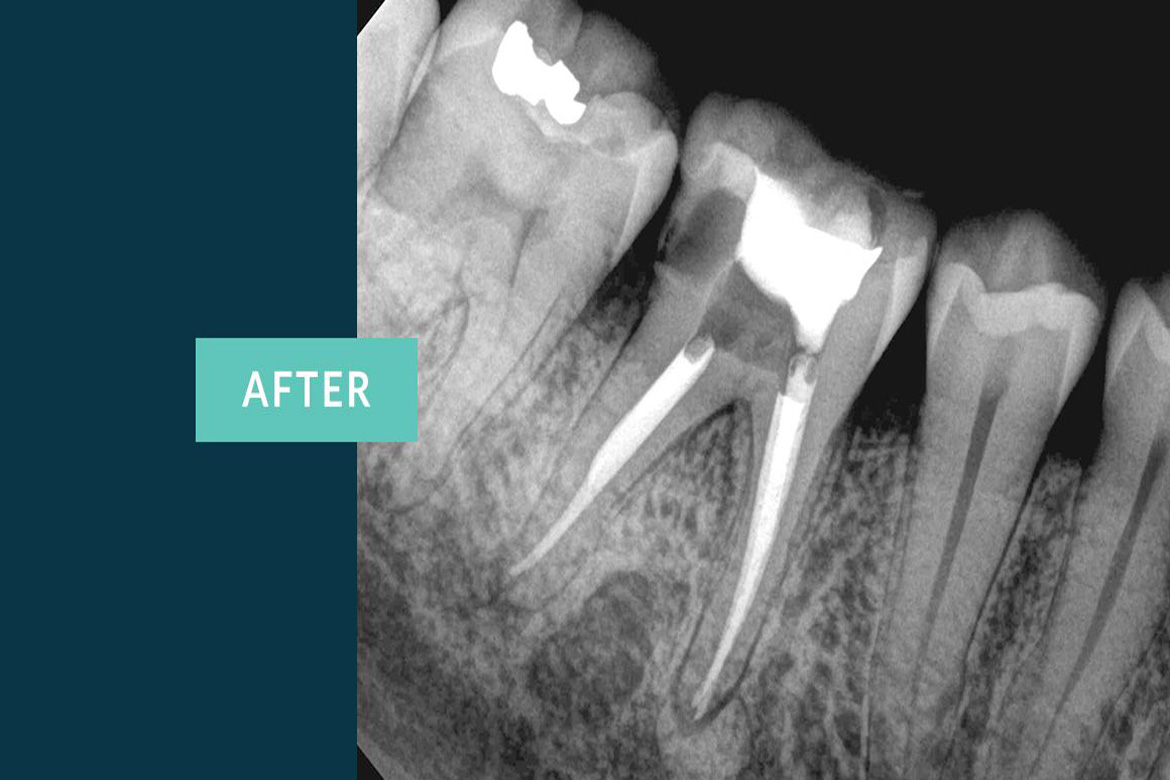

The primary intent of Root canal treatment is to remove the diseased pulp ,clean ,cleanse ,irrigate shape and then fill the canals of the tooth.

Root canal is filled completely with an inert material called Guttaperchathis is to advocate periradicular healing and prevent reinfection of the tooth there by preserving the natural tooth thus maintaining the balance in the oral cavity.

Dentistry has evolved tremendously over the past few years and the people suffering from dental pain no longer have to panic to visit a dentist and undergo multiple sittings for a Root canal treatment as it can now be done in a SINGLE SITTING.

Thanks to the advanced technology which introduced Nickel-Titanium rotary instuments,apexlocators,ultrasonics,lasers and microscopic endodontics which maked the work of a Dentist easy and hasslefree . These latest inventions helped the dentists achieve dental procedures more precisely than before.